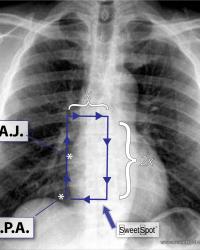

Sweet Spot |